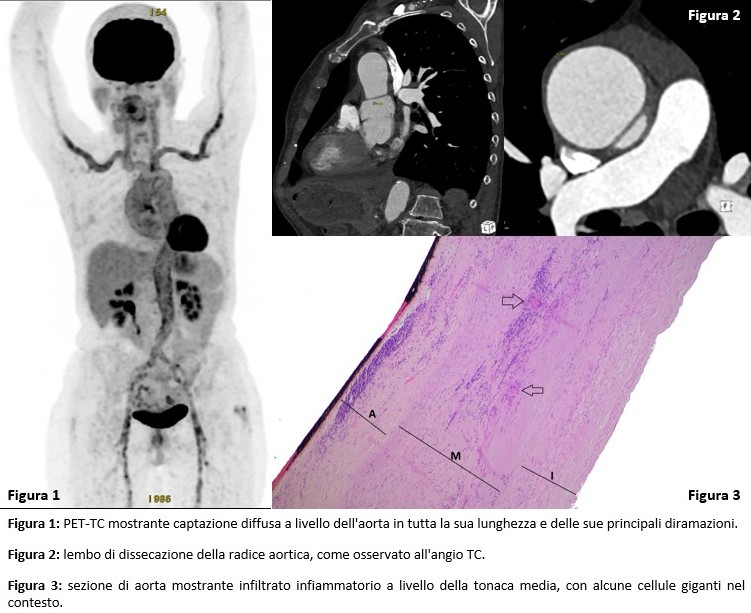

PO:37:257 | Giant cell arteritis debuting with aortic involvement: the importance of integrated diagnostics in fever of unknown origin